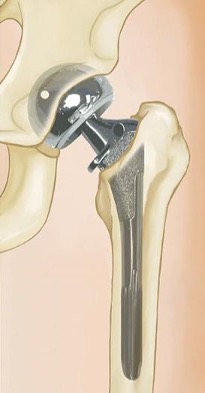

Also known as a sub-capital or intracapsular fracture. There are two ways in which this kind of hip fracture is treated.

- Displaced Femoral Neck – Elderly patients suffering from displaced fractures of the femoral neck are typically advised to undergo a hemiarthroplasty or partial hip replacement; however, certain individuals may experience greater functionality with total hip replacement despite an increased risk of complications. Total hip replacement is also highly recommended for younger and more active patients.